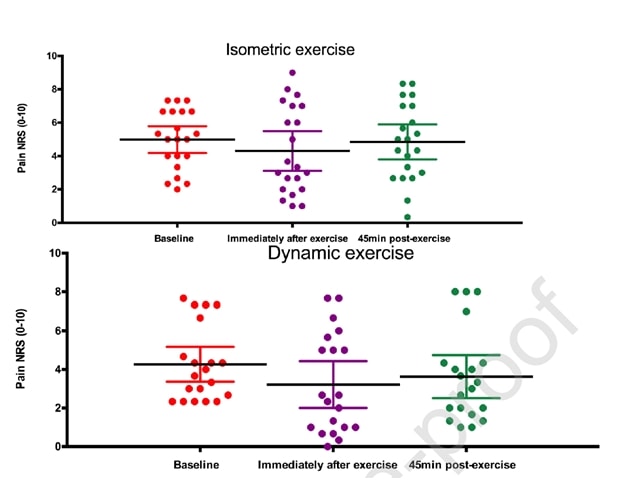

Рио и др. (2015) положили начало некоторой тенденции, когда провели перекрестное исследование на 6 волейболистах с тендинопатией надколенника. Их результаты были поразительными: у всех игроков сразу же уменьшилась боль - в среднем с 7/10 по NRS до 0, и только один из 6 человек сообщил, что после изометрических сокращений боль оставалась на уровне 1- в течение как минимум 45 минут. Протокол, который они использовали, состоял из 5 сетов с 45-секундным сокращением в тренажере для разгибания ног и усилием в 70% от максимального добровольного усилия. Они также обнаружили, что изометрия способна уменьшить торможение коры головного мозга и увеличить силу на 19%. Они сравнили изометрическое вмешательство с изотоническим, и эффекты, наблюдаемые в изометрической группе, не могли быть достигнуты в изотонической группе:

Те же авторы провели повторное исследование в течение сезона с прыжковыми спортсменами два года спустя (Rio et al. 2017), в котором они сравнивали между собой изометрическую программу и изотоническую программу. В этом исследовании результаты были немного более неоднородными в обеих группах с большим немедленным уменьшением боли в изометрической группе:

Недавнее исследование Холдена и др. (2019) рассмотрели эффект изометрии и при тендинопатии надколенника и не обнаружили никакого обезболивающего эффекта:

Рисунок из книги Holden et al. (2019)

Однако большой процент женщин и относительно высокий средний возраст нетипичны для тендинопатии надколенника, которая обычно является болезнью молодых прыгучих мужчин. Так что не исключено, что в некоторых случаях диагноз тендинопатии надколенника был поставлен неверно. Хотя эти два исследования проводились для тендинопатии надколенника, давай посмотрим, сможем ли мы перенести эти результаты на другие сухожилия.